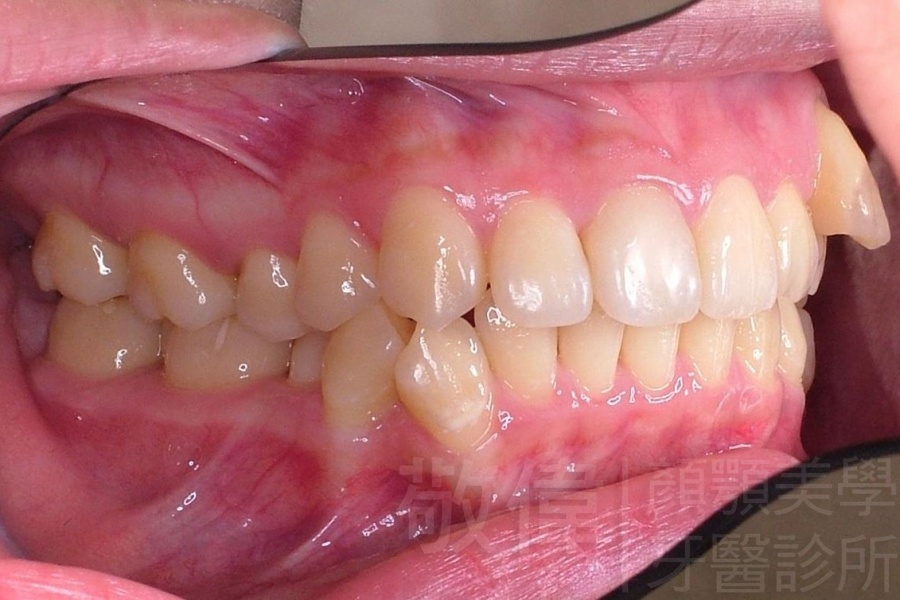

齒顏矯正/戽斗臉型 變身 大帥哥

矯正前-右   矯正前-正   矯正前-左

矯正後-右   矯正後-正   矯正後-左

<個案說明>

戽斗(學名第三級咬合 class III)矯正之後,戽斗的樣子就比較沒有了。最主要的改變是在牙齒的咬合。從側面比較,治療前、治療後的臉型 可更明顯看出來 戽斗的感覺 減少了很多。